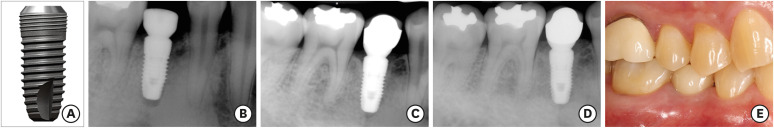

Purpose: This study retrospectively investigated the long-term clinical and radiographic outcomes of a bone-level type, 2-piece, internal connection dental implant system characterized by coronal microthreads.

Methods: A total of 872 implants placed in 284 patients were selected from 1,845 implants placed in 691 patients by experienced periodontists at Yonsei University Dental Hospital. These selected implants had been followed up for over 10 years and were included in the present study. A statistical evaluation of implant survival and treatment success, based on changes in marginal bone levels, was conducted using electronic records and consecutively taken radiographs.

Results: Over a follow-up period of 12.3±2.0 years, 830 of the 872 implants remained intact, yielding a cumulative survival rate of 95.2% at the implant level and 88.4% at the patient level. The cumulative treatment success rates, characterized by marginal bone loss of less than 2 mm, stood at 87.0% for implants and 76.1% for patients. Among the 830 surviving implants, 113 fixtures were classified as ailing, with an average marginal bone loss of 4.09±1.44 mm. Cox regression analysis revealed that implants 8 mm in length or shorter were significantly more likely to fail or experience pathologic marginal bone resorption, with hazard ratios of 3.71 and 2.00, respectively (P<0.05).

Conclusions: The survival and treatment success of the investigated microthreaded, bone-level, 2-piece, internal connection implants were acceptable over a follow-up period exceeding 10 years. However, shorter dental implants exhibited a higher propensity for failure and excessive marginal bone loss.